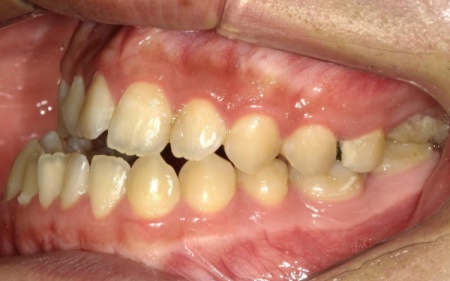

10代男性 顎変形症が原因で下顎がずれて非対称になっていた噛み合わせをサージェリーファースト法を併用した矯正治療で改善した症例

「顔と顎がゆがんでいて、見た目が悪くしゃべりにくいのが気になる。また、前歯が噛み合っていないため、食べ物を噛み切ることができない」とご相談いただきました。

拝見したところ、骨格の問題により下前歯が上前歯より前に出ている前歯部反対咬合と、前歯が開いて噛み合わないオープンバイトが認められました。

さらに、下顎の骨が右方向にずれて上下の歯が噛み合う面が斜めになっていることで、顔面の非対称も見られます。

これらは顎変形症と呼ばれる状態で、現在は食べ物をしっかりと噛む機能が大きく制限されているうえ、発音や見た目に悪影響が出ていました。